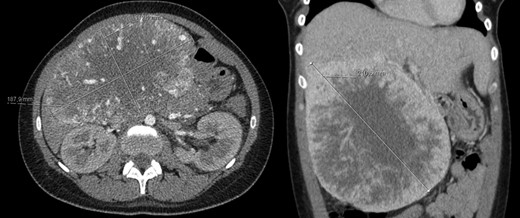

A 26-year-old woman, with past medical history of removal of hemangiopericytoma of the right leg, was referred to our Hepatobiliary Unit due to a liver tumor that was discovered on abdominal-pelvic computed tomography (CT) scan, performed after complaints of epigastric pain. CT scan (Fig. 1) showed a voluminous, heterogeneous, hypervascular mass, occupying segments 4, 5 and 8, with 19 cm in diameter, as well as suspicious lesion on left iliac bone suggestive of solitary fibrous tumor metastasis.

Abdomino-pelvic computed tomography (AP-CT) – voluminous heterogeneous liver mass in segments 4, 5 and 8 with 19 cm in diameter.